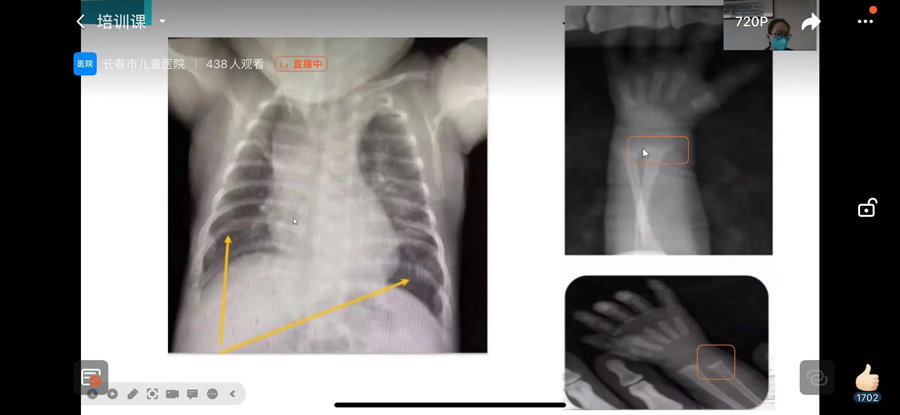

“肺炎支原体肺炎是儿童常见的社区获得性肺炎,多发于秋冬季,其他季节均有散发病例……”黄艳智详细解读了《儿童肺炎支原体肺炎诊疗指南(2023版)》。同时,从肺炎支原体肺炎的发病现状、流行时间、发病机制、病理表现、临床表现、影像学表现、支气管镜下表现、诊断、支原体抗体检查结果解读、支原体肺炎的临床分型、重症和危重症的早期预警指标、鉴别诊断、治疗原则等方面给予了科学具体的指导。通过此次培训,进一步提高发长春地区儿科医疗机构从业人员关于儿童肺炎支原体肺炎诊疗规范化水平,从而保障医疗质量的安全。

牟婷对《早产儿代谢性骨病》进行了解读。同时从实例、概念、流行病学、预后、高危因素、临床表现、诊断、血生化指标、尿生化指标、放射学检查、共识推荐、治疗、预防等方面进行了专业指导,为参加培训人员上了一堂干货满满的专业课。